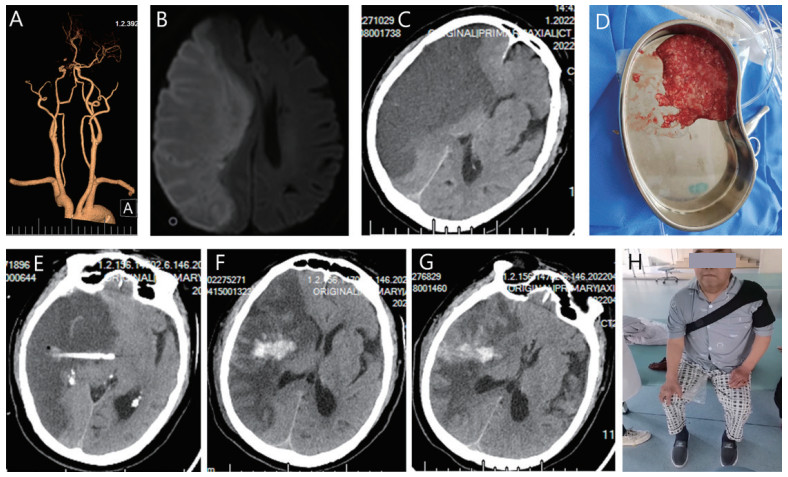

案例2:单纯抽吸治疗老年MMI患者,男,75岁,因“意识模糊伴肢体无力12 h”入院,发病后48h行左侧颞部置管抽吸坏死脑组织,6个月随访患者能独立行走,mRS评分为3分(图 2)。

A:术前CTA显示侧右侧大脑中动脉闭塞, 闭塞远端侧枝血管缺如。B:术前磁共振DWI显示梗死面积 > 2/3大脑中动脉供血区(MCA)。C:发病后28 h术前复查CT显示大面积脑梗死基础形成恶性水肿,右侧侧脑室闭塞,中线移位12 mm。D:行定向抽吸坏死组织减压术,缓慢抽出混有暗红色血液的红白相间的坏死脑组织。E:术后第2天复查,经颞部抽吸导管位于梗死区内。F:术后第5天CT显示水肿减退,中线结构及压闭的侧脑室明显恢复,经颞部引流管已经拔除, 梗死区内出血10 mL,不伴有占位效应。G:术后第8天CT显示,中线移位基本恢复正常。H:半年后随访能独立行走,mRS评分3分 图 2 单纯抽吸坏死脑组织治疗老年MMI Fig 2 Stereotactic aspiration of necrotic brain tissue for an elderly patient with MMI